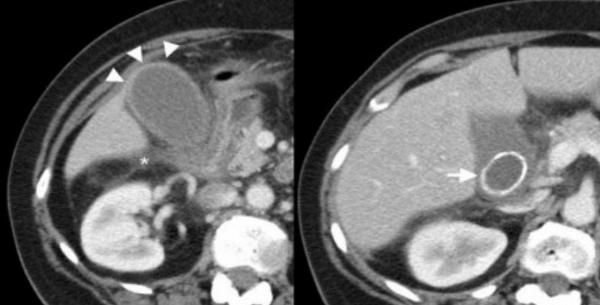

Острый калькулезный холецистит. После контрастного усиления визуализируется растянутый желчный пузырь (белые наконечники) со слегка утолщенной стенкой. Визуализируется камень в шейки желчного пузыря (белая стрелка).

Сверху изображения пациента 62 лет с калькулезным холециститом. На УЗИ визуализируется стенки желчного пузыря растянутые, с субсерозным отеком (указано белыми стрелками) и в просвете желчного пузыря камень и взвесь. На КТ визуализируется переход воспалительного процесса с желчного пузыря на соседние ткани (перихолецистит).